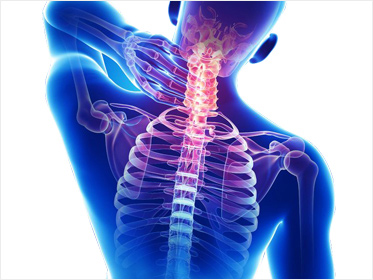

�߳����

�����ѹ溴���� ���õ� ���ǻ簡 ô�� ��ũ�� ������ �ٷ�����ϴ�.

�߳������?

��Ծ��� ô�� �� ������ ������ �а� ��� ���� ������ �ٷ���� ������ ���߾� ô�߿� ô�� �ֺ������� ����� �����ϰ� �����ϴ� �������Դϴ�.

�߳���� ġ�� ����

ô�߿� ������ ������ �ٸ��� �����ν� ������ ġ���ϴ� ���� �������� �մϴ�. ��ü�� �¿� �뷱���� �������ν� ����� ������Ѽ� ������ȯ�� ��Ȱ�ϰ� �ϴ� ġ����Դϴ�.

�߳���� ġ�� ȿ��

�߳������ �������� ���� ���� �̿Ͻ��������� Ʋ���� ������ ����ȭ��Ű�� ������ �������� ���������� ������Ű��, �� ���� ���� ȸ��, ��� ����, ���� ��ȭ ���� ȿ���� �� �� �ֽ��ϴ�.